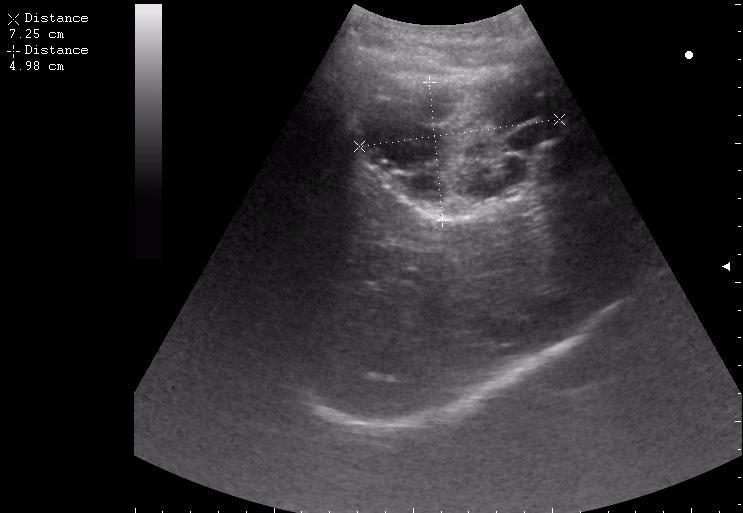

17-летняя девушка с множественными поражениями печени